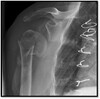

Q

What pathology is shown here?

Osteosarcoma